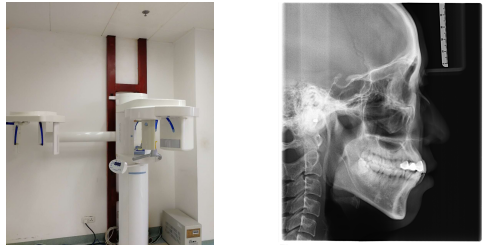

2、数字化口腔全景机:可拍摄口腔全景片、头颅定位测量片、颞下颌关节片及头颅后前位片、瓦特氏位片等。